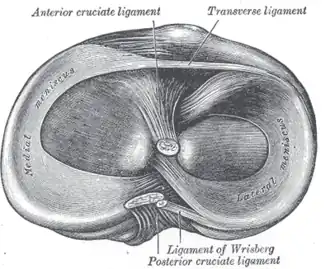

Head of right tibia seen from above, showing menisci and attachments of ligaments

Head of right tibia seen from above, showing menisci and attachments of ligaments -